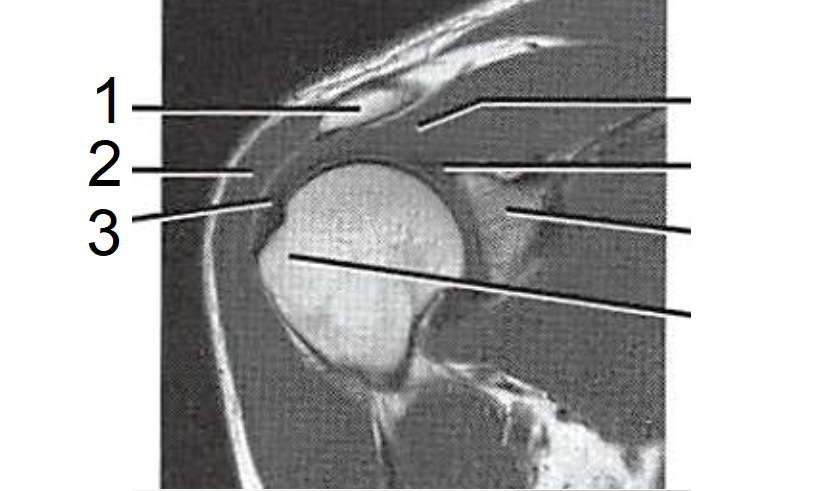

5

1 - Acrômio

2 - M. deltoide

3 - Tendão do M. supraespinhal

How well did you know this?